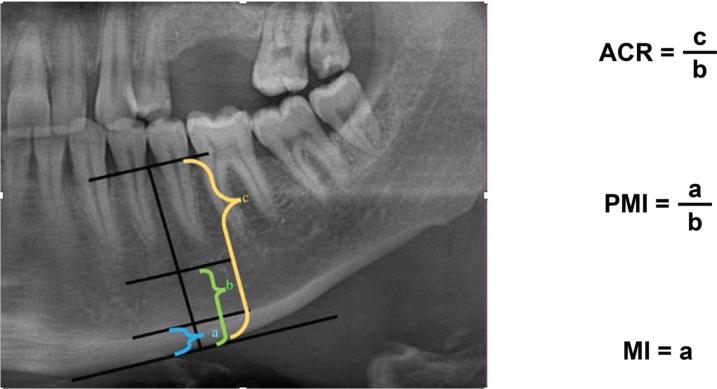

Knowledge about oral hygiene, gingival bleeding, mineral density, and resorption of jaw bones in patients with hemophilia is limited. We evaluated the periodontal and bone status in such patients. Material and methods: Forty-eight patients with severe type A/B hemophilia and 49 age- and sex-matched controls were included. Assessments included simplified oral hygiene index (OHI-S), calculus index, debris index, gingival index (GI), gingival bleeding time index (GBTI), and decayed, missing, and filled teeth index (DMFTI). Bone resorption was evaluated using panoramic mandibular index (PMI), mental index (MI), and alveolar crest ratio (ACR). Mineral density in the condyle, angulus, and premolar areas was assessed using fractal analysis, with fractal dimensions denoted as condyle fractal dimension (CFD) for the condyle, angulus fractal dimension (AFD) for angulus, and premolar fractal dimension (PFD) for premolar region.

The mean scores were DMFTI = 11.77, OHI-S = 2.44, PMI = 0.268, MI = 5.822, GI = 3.02, GBTI = 2.64, ACR = 2.06, CFD = 1.31, AFD = 1.31, and PFD = 1.17 in the hemophilia group and DMFTI = 11.449, PMI = 0.494, MI = 7.43, GI = 0.67, GBTI = 0.98, OHI-S = 1.45, ACR = 2.87, CFD = 1.35, AFD = 1.35, and PDF = 1.23 in the control group. Differences were significant for all parameters (p < 0.005) except for the DMFTI index. Conclusions: Because of poor oral hygiene, high bone resorption, and low bone mineral density in these patients, clinicians should consider potential bone changes when planning to treat these patients.